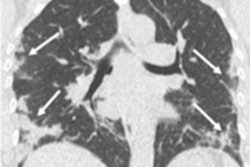

Reverse transcription polymerase chain reaction (RT-PCR) assays are considered the best way to identify COVID-19, but it can take time to get results, and a negative test doesn't necessarily exclude the disease, the team noted. CT offers a way to detect COVID-19 in patients manifesting symptoms.